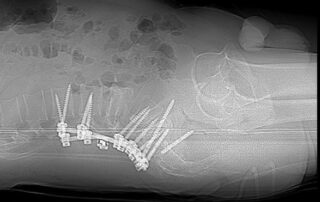

Леонтьєв Олексій2024-09-18T11:46:10+03:00До відділення звернувся пацієнт, який отримав важке вогнепальне поранення хребта та живота. Пацієнт отримав хірургічне лікування у військовому шпиталі, де також було виконано стабілізацію ушкодженого хребта. Але, [...]